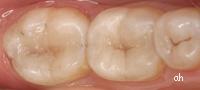

- De nouveaux composites (résines blanches) permettent avantageusement de reconstruire une dent cariée de façon étanche et esthétique.

En voici quelques exemples:

cliquer sur les photos pour faire apparaître les commentaires

anicenne obturation en composite

fraisage léger de la dent

le nouveau composite en place